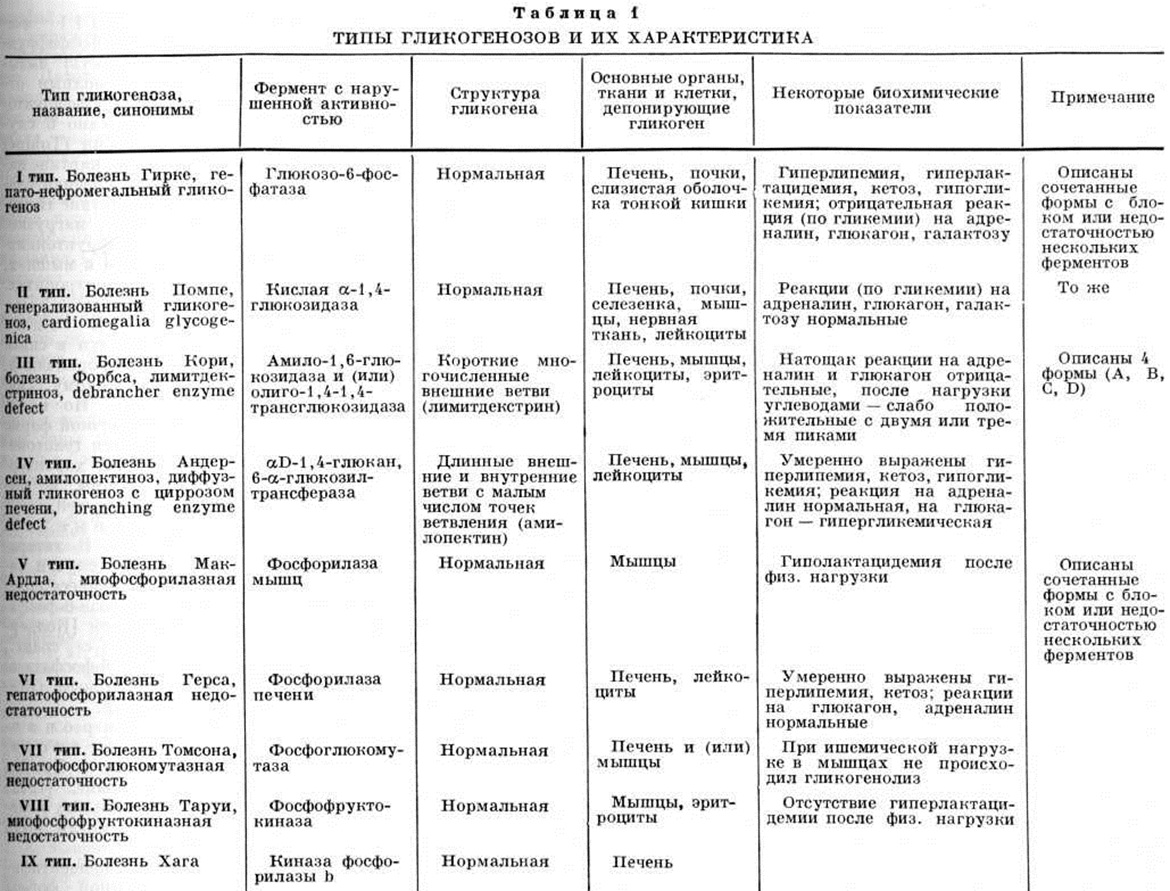

Распространённость Гликогеноз в популяции составляет 1 : 40 000. Выделено 12 типов Гликогеноз, наиболее полно изучены 9 (таблица 1); типы X (изолированный Гликогеноз сердца) и XI (дефицит фосфофруктокиназы), возможно, являются вариантами основных форм Гликогеноз. Типы гликогенозовРазличают три основные формы Гликогеноз: печёночную, мышечную и генерализованную. Гликогеноз I типа (болезнь Гирке, гепатонефромегальный Гликогеноз) связан с дефицитом активности глюкозо-6-фосфатазы печени и почек, что может быть установлено при жизни с помощью гистохимические исследования материала, полученного при биопсии этих органов. Наследуется по аутосомно-рецессивному типу. По клинической картине это заболевание относят к печёночной форме Гликогеноз. Первые проявления его — отсутствие аппетита, рвота, гипогликемические судороги (комы), респираторный дистресс-синдром (смотри полный свод знаний), интермиттирующее повышение температуры, гепатомегалия, нефромегалия, стеаторея (смотри полный свод знаний), кетонурия (смотри полный свод знаний Ацетонурия) — выявляются сразу же после рождения или в грудном возрасте. |

Гликогеноз II типа (болезнь Помпе, генерализованный гликогеноз, cardiomegalia glycogenica) развивается в связи с дефицитом кислой α-1,4-глюкозидазы. Наследование аутосомно-рецессивное, отмечается связь с частотой возникновения эндокардиального фиброэластоза [Динской (М. Y. Dinscoy) с соавт., 1965].

Гликогеноз III типа (болезнь Кори, болезнь Форбса, лемитдекстриноз, debrancher enzyme defect) вызывается полным или частичным отсутствием активности амило-1, 6-глюкозидазы и (или) олиго-1,4-1,4-трансглюкозидазы. Установлено 4 подтипа заболевания (таблица 2). Генетический анализ этого типа Гликогеноз труден из-за наличия нескольких его форм. По клинический, картине относят к мышечной или печеночной форме Гликогеноз

Гликогеноз IV типа (болезнь Андерсена, амилопектиноз, диффузный гликогеноз с циррозом печени, branching enzyme defect) вызывается отсутствием αD-1,4-глюкан, 6-α-глюкозилтрансферазы. Предполагается аутосомно-рецессивный или связанный с полом тип наследования.

Гликогеноз V типа (болезнь Мак-Ардла, миофосфорилазная недостаточность) развивается в связи с дефицитом мышечной фосфорилазы. Активность печёночной фосфорилазы не изменена. Аутосомно-рецессивный тип наследования. Лица мужского пола болеют в 5 раз чаще. В связи с гликогенной инфильтрацией скелетные мышцы увеличиваются в объёме, становятся резко плотными. По клинический, картине заболевание относят к мышечной форме Гликогеноз Симптомы его — мышечная слабость, мышечные спазмы, тахикардия — появляются в первые десять дней жизни и прогрессируют. Появляется транзиторная миоглобинурия [Мак-Ардл (В. Mac Ardle), 1951; Пирсон (С. М. Pearson) с сотрудники, 1961]. Концентрация лактата в крови уменьшается после физических нагрузки. Окончательный диагноз возможен при исследовании фосфорилазной активности в мышечных биоптатах; в гомогенатах мышц гликоген не превращается в лактат.

Гликогеноз VI типа (болезнь Герса, гепатофосфорилазная недостаточность) вызывается недостаточностью фосфорилазы в печени. Предполагается аутосомно-рецессивный тип наследования. По клинический, картине относят к печёночной форме Гликогеноз Характерны значительная гепатомегалия в результате гликогенной инфильтрации гепатоцитов, задержка роста, кукольное лицо, гиперлипемия, гипергликемия (после внутривенного введения галактозы), повышенное содержание гликогена в эритроцитах. Прогноз сомнителен.

Гликогеноз VII типа (болезнь Томсона) развивается в связи с дефицитом фосфоглюкомутазы в печени и (или) мышцах. Впервые описан в 1963 год Томсоном (W. Н. S. Thomson) с соавторами у мальчика с миопатией. В 1964 год Иллингворт (В. Illingworth) и Браун (D. Н. Brown) описали мальчика, больного Гликогеноз с гепатомегалией. Встречается редко.

Гликогеноз VIII тип а (болезнь Таруи, миофосфофруктокиназная недостаточность) вызывается дефицитом или полным отсутствием активности фосфофруктокиназы в мышцах. Описано 6 случаев этого типа Гликогеноз [Тобин (Tobine) с соавторами, 1973]. По клинический, картине напоминает Гликогеноз V типа: мышечная слабость, утомление и отсутствие гиперлактацидемии после физ. нагрузки. Низкий уровень фосфофруктокиназы у больных обнаружен в мышцах, у их родителей — в эритроцитах. Прогноз благоприятный.

Гликогеноз IX типа (болезнь Хага) развивается в связи с дефицитом киназы фосфорилазы b. Наследуется по рецессивному, связанному с полом типу. По клинический, картине относят к печёночной форме Гликогеноз. У больных наблюдается гепатомегалия. Другие симптомы, характерные для печёночной формы, не выражены. Прогноз неизвестен.